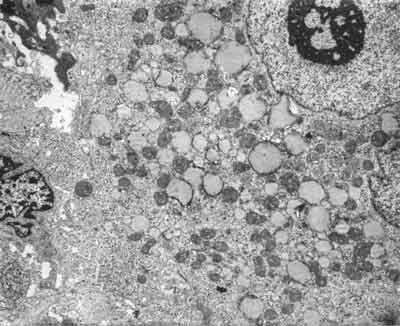

Histologisch bietet die Schwangerschaftsleber

ein normales Bild. Elektronenoptisch finden sich

jedoch bei ca. drei Vierteln der Schwangeren im letzten Trimenon

mitochondriale Veränderungen in Form von Vergrößerungen,

Verformungen und kristallinen Einschlüssen. Es dürfte

sich um adaptive Veränderungen handeln, wahrscheinlich bedingt

durch die erhöhten Steroidhormonspiegel, denen kein Krankheitswert

zukommt und die sich nach der Geburt vollständig zurückbilden

(Abb. 1.1) (69, 70, 74). Eine besondere Ausprägung

erfahren diese strukturellen Alterationen der Mitochondrien im Rahmen

der intrahepatischen Schwangerschaftscholestase (s. Kap. 1.3.1.),

möglicherweise sind sie auch pathogenetisch bedeutsam bei der

akuten Schwangerschaftsfettleber (s. Kap. 1.3.3).

Abb. 1.1 Ausschnitt einer Leberparenchymzelle

bei ungestörter Schwangerschaft 8. Monat. Neben wenigen, normal

strukturierten Mitochondrien finden sich zahlreiche vergrößerte

Mitochondrien mit kristallinen Innenstrukturen und dichtem Cristae-Besatz.

Bis auf eine geringe Vakuolisierung des endoplasmatischen Retikulums

sind die übrigen Zellorganellen normal. Vergr. 13800fach.